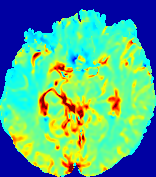

LesionRefer to captionRefer to captionRefer to captionRefer to captionRefer to captionRefer to caption𝐕rgbsubscript𝐕𝑟𝑔𝑏{\bf{V}}_{rgb}Refer to captionRefer to captionRefer to captionRefer to captionRefer to captionRefer to caption𝐕2subscriptnorm𝐕2{\|\bf{V}}\|_{2}Refer to captionRefer to captionRefer to captionRefer to captionRefer to captionRefer to captionRefer to caption3.53.53.52.82.82.82.12.12.11.41.41.40.70.70.70.00.00.0(mm/s)𝑚𝑚𝑠(mm/s)D𝐷DRefer to captionRefer to captionRefer to captionRefer to captionRefer to captionRefer to captionRefer to caption0.0200.0200.0200.0160.0160.0160.0120.0120.0120.0080.0080.0080.0040.0040.0040.0000.0000.000(mm2/s)𝑚superscript𝑚2𝑠(mm^{2}/s)Slice #1Slice #2Slice #3Slice #4Slice #5Slice #6

Figure 4: PIANO feature maps for another patient in the ISLES 2017 training set, where the lesion is located in the right hemisphere. Top row: segmented stroke lesion region (white) on different slices. The corresponding slices for the PIANO feature maps are shown in the following rows.

For a better insight into an estimated velocity field 𝐕𝐕{\bf{V}} and diffusion field 𝐃𝐃{\bf{D}}, we compute the following maps: (1) 𝐕rgbsubscript𝐕𝑟𝑔𝑏{\bf{V}}_{rgb}: Color-coded orientation map of 𝐕=(Vx,Vy,Vz)T𝐕superscriptsuperscript𝑉𝑥superscript𝑉𝑦superscript𝑉𝑧𝑇{\bf{V}}=(V^{x},V^{y},V^{z})^{T}, obtained by normalizing 𝐕𝐕{\bf{V}} to unit length and mapping its 3 components to red, green, blue respectively; (2) 𝐕2subscriptnorm𝐕2\|{\bf{V}}\|_{2}: 222 norm of 𝐕𝐕{\bf{V}}; (3) D𝐷D: scalar field in Eq. 5.

Fig. 3 and Fig. 4 show the PIANO feature maps estimated from two ISLES 2017 patients: all are highly consistent with the lesion in both cases. Details of the blood flow trajectories are revealed in 𝐕rgbsubscript𝐕𝑟𝑔𝑏{\bf{V}}_{rgb} by the ridged patterns and the sharp changes of colors in the unaffected (right) hemisphere, while the flat patterns appearing within the lesion provide little directional information about the velocity and indicate low velocity magnitudes. Velocity magnitudes are more directly visualized via 𝐕2subscriptnorm𝐕2\|{\bf{V}}\|_{2}, from which one can easily locate the lesion where 𝐕2subscriptnorm𝐕2\|{\bf{V}}\|_{2} is low. D𝐷D also indicates lower diffusion values in the lesion, though with less contrast potentially due to the fact that it captures the accumulated effect of CA diffusion at the voxel-level.